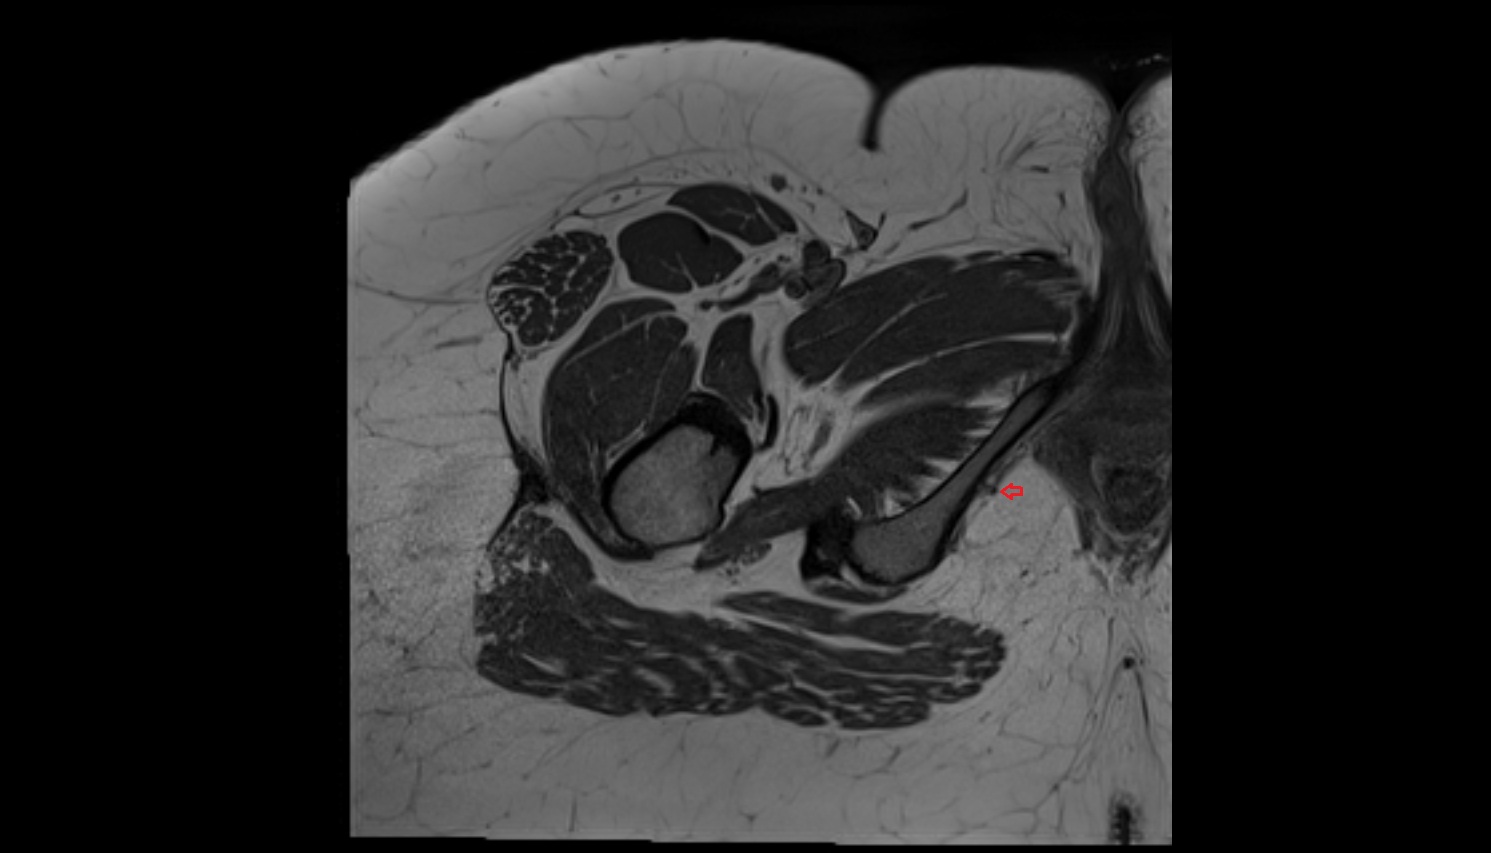

- External iliac artery

- Internal iliac artery

- Femoral artery

- Medial circumflex femoral artery

- Obturator artery

- Superficial femoral artery

- Pudendal artery

- Superior gluteal artery

- Sciatic nerve

- Pudendal nerve

- Obturator nerve